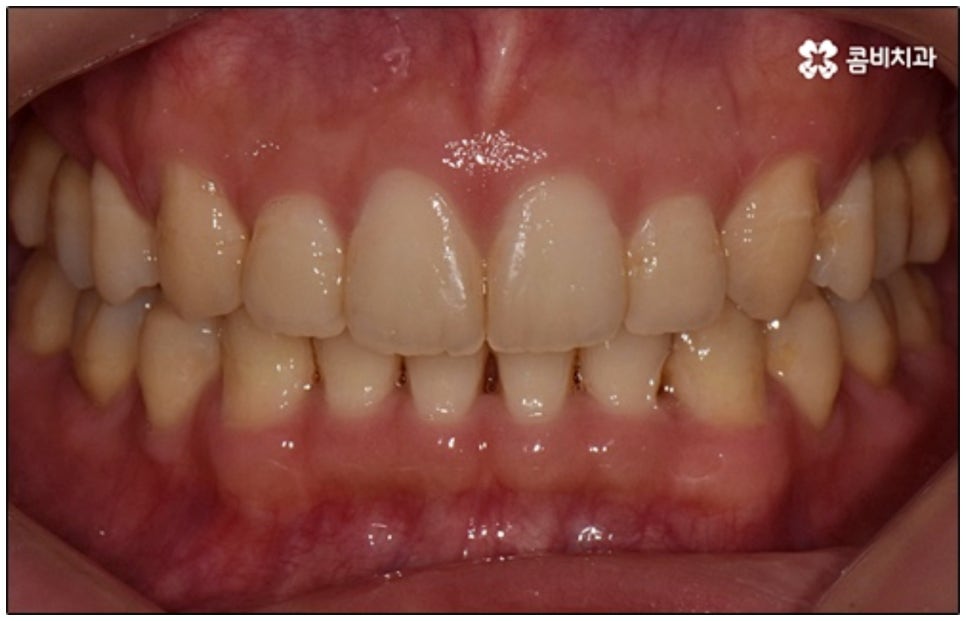

말씀드린 것과 같은 다양한 이점들이 있기 때문에 현재 본원의 교정 환자분들은 대부분 클리피씨교정 장치를 이용하여 치료를 진행하고 있습니다. 사진 역시 돌출입 교정을 위해 발치 후 클리피씨교정 장치를 이용하신 환자분의 케이스인데 시간이 지날수록 점차 앞니가 자연스럽게 들어가고 위아래 교합이 정확하게 맞아가는 것을 확인하실 수 있을 거예요.